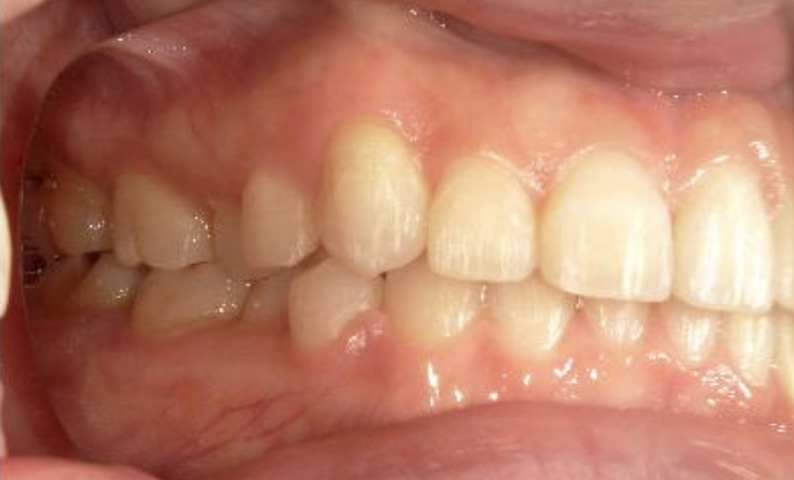

症例_023 上下顎の部分矯正

治療期間:11ヶ月金額:45万円+税女性前歯のガタガタ八重歯

| Before | After |